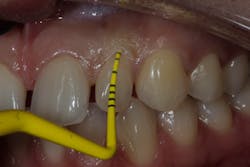

• Type 1 socket—Buccal plate present and soft tissue present

Type 1a (figure 7)—Thick biotype, posterior tooth, and buccal plate present: no graft needed